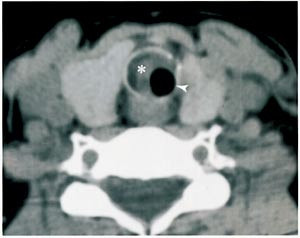

På bakgrunn av resultatene fra spirometrien ble det utført computertomografi (CT) av trachea, og det ble påvist en 2 cm lang stenose (fig 2). Bronkoskopi viste uttalt subglottisk trakeal stenose med kun en liten rund åpning baktil medialt. Funnet var forenlig med sekvele etter tidligere gjennomgått intubasjon. Makroskopisk forelå det ingen tumormistanke, og biopsi ble ikke tatt. Endoskopisk laserterapi ble utført, og pasienten opplevde betydelig bedring av sine plager.